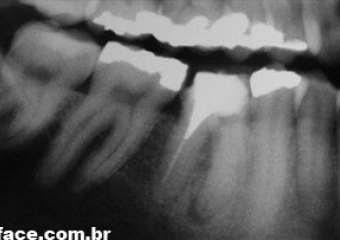

Raio X inicial

Raio X periapical inicial